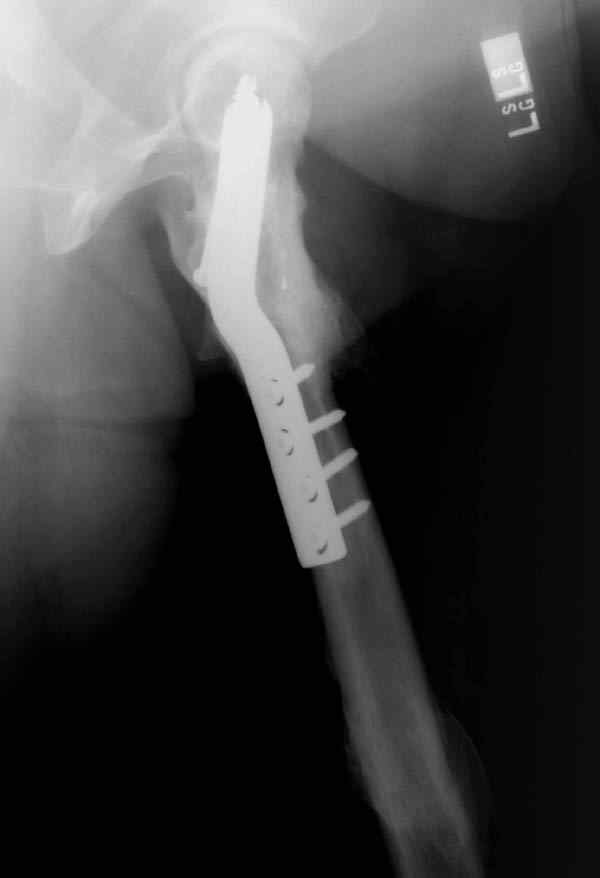

Учитывая молодой возраст больного, из всех рекомендуемых вариантов для лечения ложного сустава шейки предпочтительным является вальгусная остеотомия (на сайте имеются прежние разборы) из-за простоты исполнения и биомехнических преимуществ.

После удаления штифта нет необходимости проведения "стресса" на сращение, лучше провести фиксацию пластиной по два шурупа с каждой стороны.

Минимальный перкутанный доступ без ущерба сохранит сомнительное мозолеобразование и создаст условия для профилактики ложного сустава бедра.

Или при наличии ретроградной техники, короткий штифт с одним блокирующим шурупом дистально, создаст адекватную фиксацию и условия для быстрейшего восстановления.